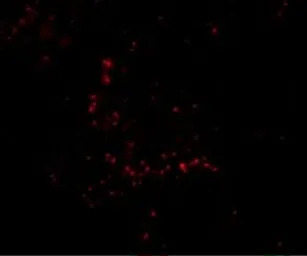

IHC-P analysis of mouse ovary tissue using GTX85386 TRIM30 antibody.

Working concentration : 10 μg/ml